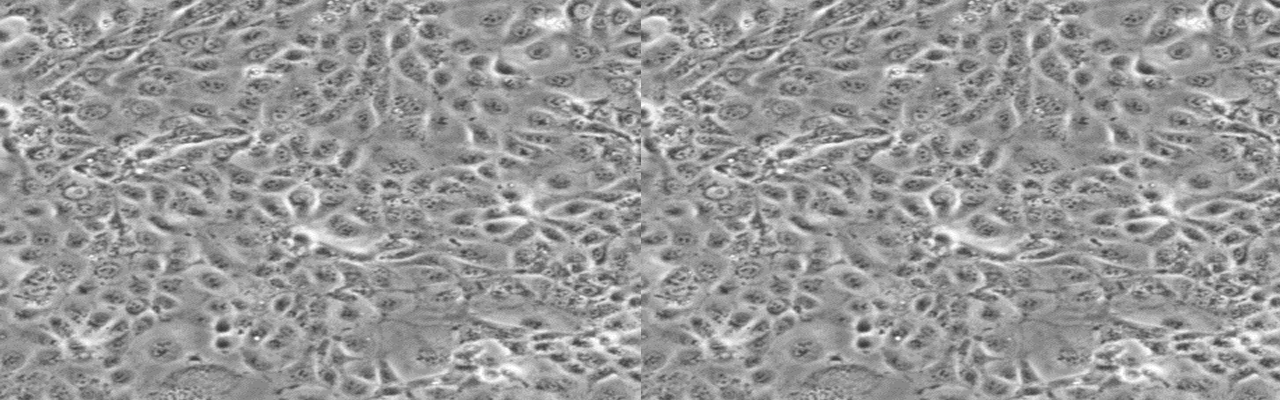

| 名称 | NCI-H3255 |

| 细胞全名 | NCI-H3255 人肺癌细胞株 |

| 生长特性: | 贴壁生长 |